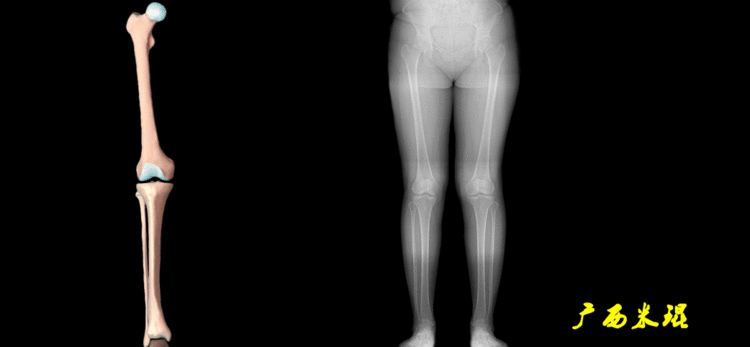

4、画出与机械轴相关的角度股骨近端外侧角(LPFA):沿股骨头中心与大粗隆最高点划一直线,连接股骨头中心与膝关节中心划一直线(机械轴),两者之间形成的外侧夹角,正常为90°±5°。

股骨远端外侧角(mLDFA):股骨内外侧髁远端切线(关节线)与股骨头和膝关节中心的连线(机械轴)两者之间形成的外侧夹角,正常为87°±3°。

胫骨近端内侧角(mMPTA):胫骨内外侧平台切线(关节线)与股骨头和膝关节中心的连线(机械轴)两者之间形成的内侧夹角,正常为87°±3°。

胫骨远端外侧角(mLDTA):胫骨远端切线(关节线)与下肢力线(机械轴)两者之间的外侧夹角,正常为89°±3°。

股骨解剖机械轴角(aMFA):股骨解剖轴与机械轴形成的夹角,正常为6°±1°。

股骨垂直机械轴角(MA):股骨机械轴与身体垂直轴形成的外翻角,正常为3°。